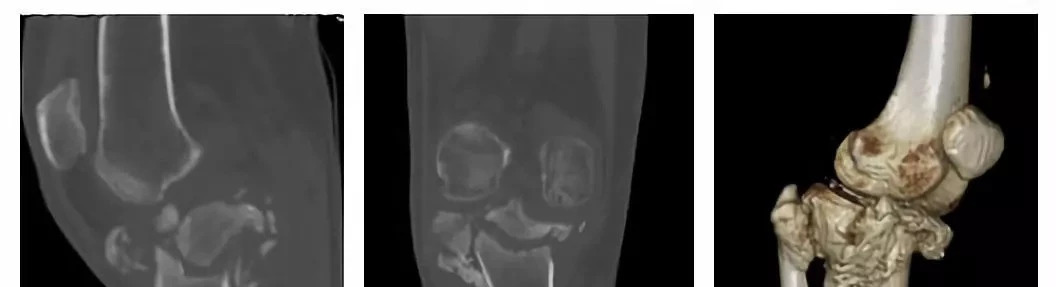

膝关节术前CT片

陈先生抱着一丝希望找到了骨科主任关振鹏教授并入住病房。入院检查显示陈先生有严重的下肢畸形,膝关节肿大、积液,双下肢乏力,膝周痛觉缺失,关节活动障碍,情况非常复杂。影像学提示膝关节对位不良,关节半脱位,关节间隙不规则,胫骨上段干骺端结构紊乱、胫骨平台大面积塌陷,呈现陈旧性粉碎骨折表现,局部骨缺损严重。在仔细分析陈先生的病情后,关主任鼓励陈先生要重燃战胜疾病的信心,准备为他实施人工膝关节置换手术,帮助他重新站起来!

3D技术打印模型

根据陈先生的病情,关振鹏主任率领骨科团队首先为他定制了3D打印的病损膝关节模型,3D模型清晰地显示了陈先生病情的严重性与复杂性,手术的难度非常高。关主任细致地为患者制定了手术方案,通过3D模型为患者量身定制了组配铰链式膝关节假体。